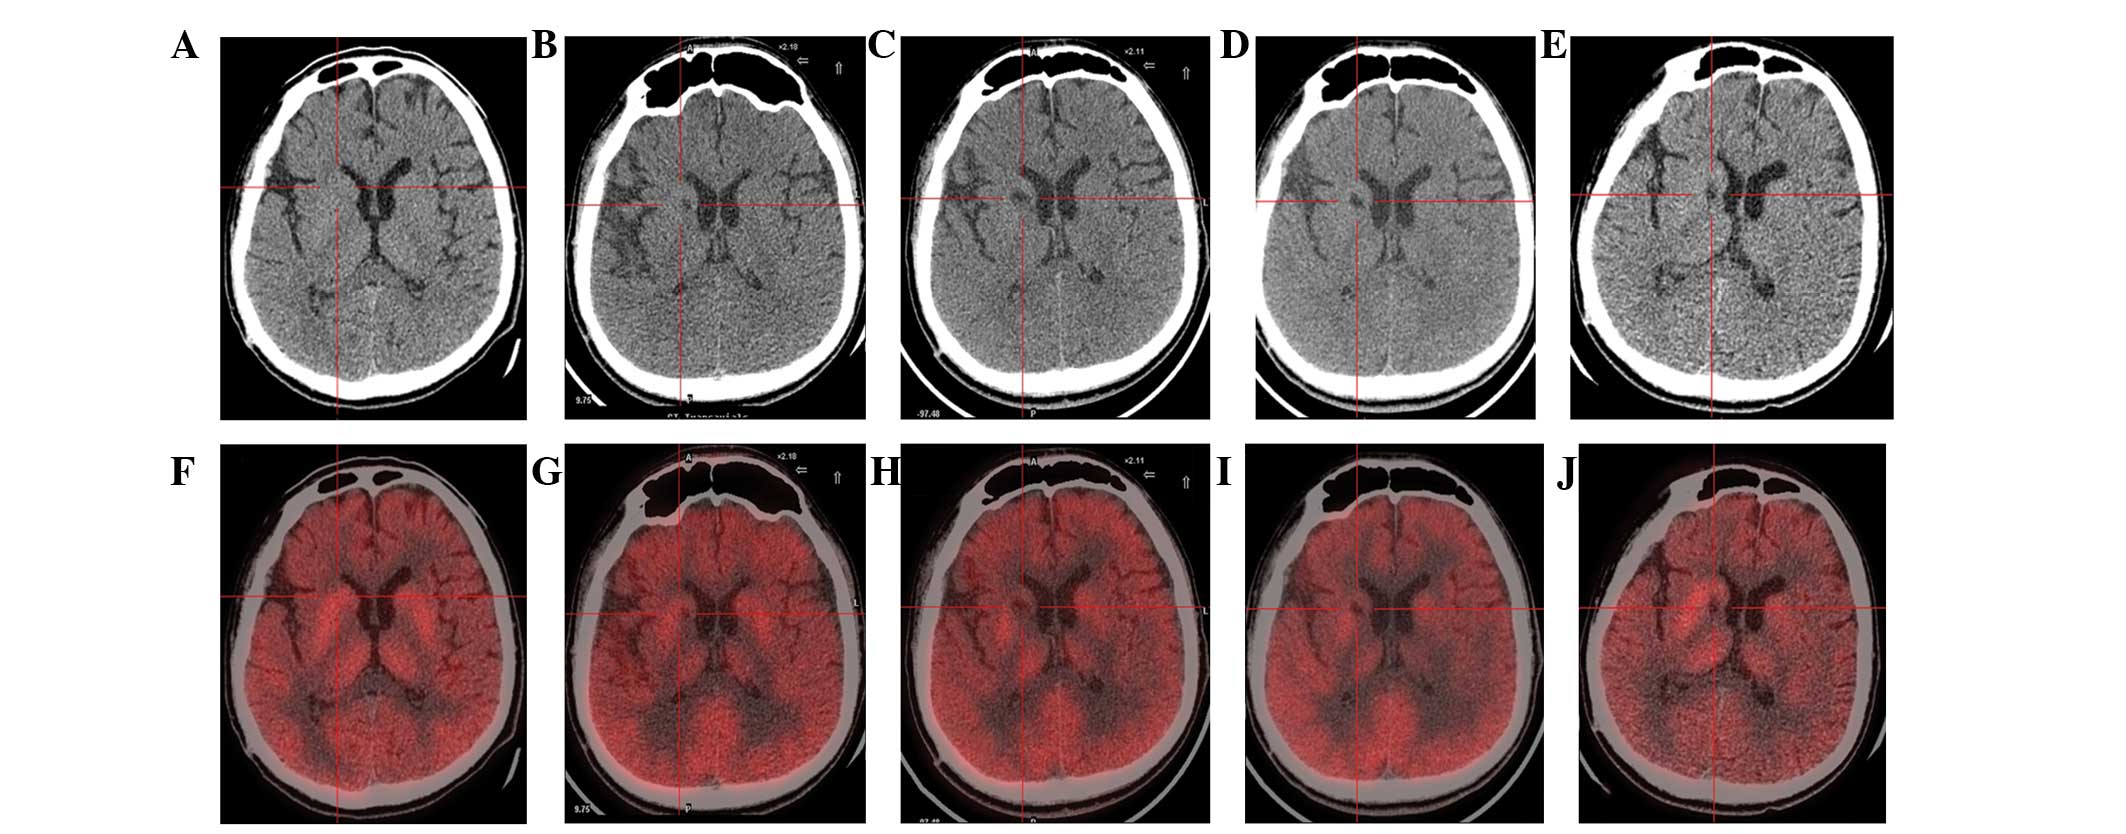

本研究選擇的患者為18歲男性,患有PTD,預產期剖宮產出生,無任何遺傳病家族史,無腦炎、黃疸、腦腫瘤病史或外傷。他在5歲時首次出現左下肢不自主痙攣和扭轉,沒有任何誘發因素。臨床特征從5歲至9歲逐漸擴展到全身。18歲時,患者無法書寫、抓握、站立或行走。他吞咽固體食物有些困難,但沒有癲癇癥狀。患者智力正常。頭部計算機斷層掃描(CT;圖1a)和磁共振成像(MRI;圖2a)提示大腦輕度萎縮。PTD是根據上述數據診斷的。

(A) 術前CT顯示腦萎縮。

(BE)術后1年、2年、3年、4年CT與術前相比均無明顯變化。

(F)術前18F-氟脫氧葡萄糖 (FDG) PET 掃描顯示,整個大腦皮層FDG攝取彌漫性減少,細胞核FDG攝取相對高于其他區域。術前1天,豆狀核和丘腦的標準化攝取值 (SUV) 平均值/最大值分別為4.3/5.8和3.3/4.5。

(GJ) 神經干細胞移植治療后分別 1、2、3 和 4 年的 18F-FDG PET 掃描顯示,雙側植入部位的豆狀核和丘腦對 18F-FDG的攝取增加(紅十字)與植入前相同部位進行比較。 豆狀核和丘腦的SUV*平均值/最大值在 1、2、分別是術后3年和4年。 該結果表明移植后葡萄糖代謝比移植前稍高。

CT(圖1b-e)和MRI(圖2b-d)掃描顯示4年隨訪期間沒有顯著變化。 手術前1天(圖1f)和手術后1、2、3和4年(圖1g-j) 獲得18F-FDGPET掃描。術后雙側植入部位豆狀核和丘腦18F-FDG攝取值較術前增加。這一結果表明,自移植以來,葡萄糖代謝逐年略有增加。